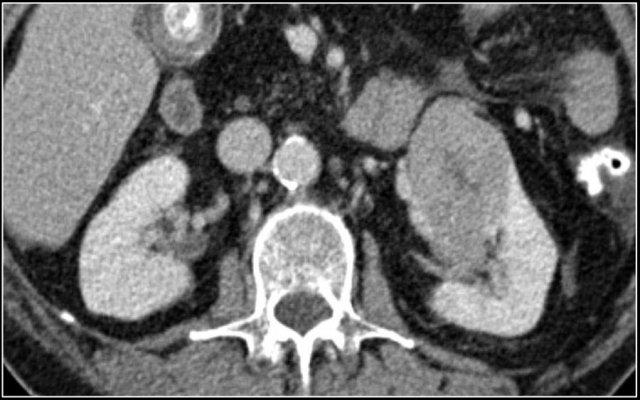

Đặc điểm điển hình của ung thư biểu mô tế bào sáng là ngấm thuốc mạnh trong thì vỏ-tủy (corticomedullary phase).

Điều này có thể khó đánh giá khi tổn thương nhỏ và nằm ở vỏ thận, vốn cũng ngấm thuốc mạnh.

Do đó, thì thận (nephrogenic phase) là thì nhạy cảm nhất để phát hiện các tổn thương này, vì nhu mô thận ngấm thuốc đồng nhất và đậm hơn so với khối u (hình minh họa).